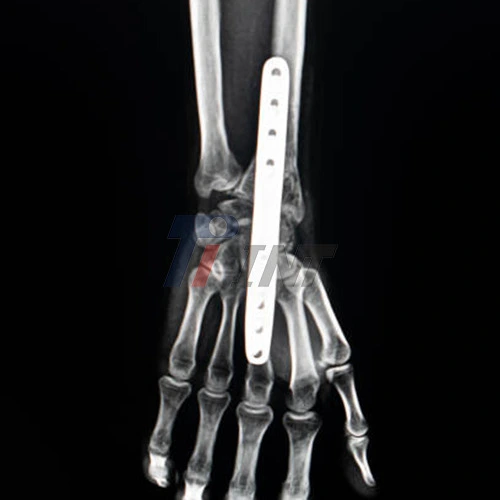

- Radiolucency: Titanium plates are less radiopaque than other metals, making them less visible on X-rays and allowing for clearer imaging, which aids in accurate follow-up examinations and better monitoring of the healing process.

- Preoperative Assessment: The surgeon evaluates the fracture through X-rays and CT scans to determine the optimal placement of the titanium plate.

- Plate Placement: The titanium plate is positioned over the fracture site and secured with screws, providing stable fixation.